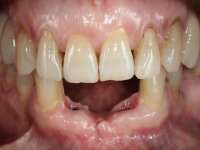

Paciente do sexo feminino com 62 anos, fumadora. 10 Anos atrás tinha sido colocado um implante na zona dos dentes 41 e 42 para reabilitar com uma ponte de dois elementos a falta destes dois dentes. Feito o exame imagiologico foi observada uma perda óssea junto ao implante compatível com uma peri-implantite. A parede óssea vestibular junto ao implante apresentava uma extensa reabsorção, estando a superfície vestibular do implante em contacto com os tecidos moles e numa determinada zona um orifício permitia a visualização do implante através do tecido gengival. Os dentes 42 e 32 apresentavam já alguma mobilidade.